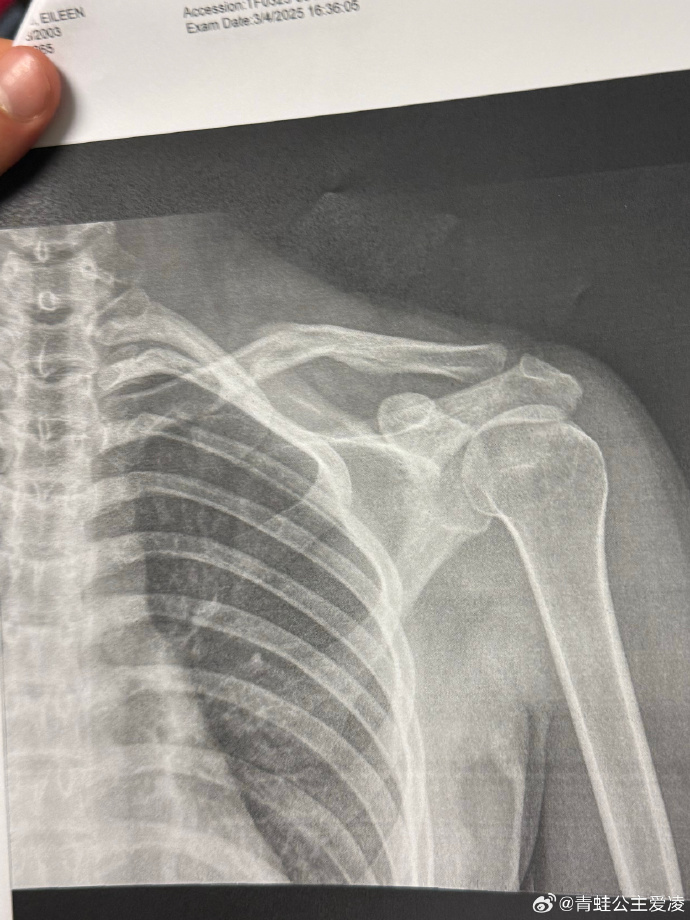

3月9日,谷爱凌在个人账号晒肩部X光片子,并配了一个心碎的表情 。片子的日期是3月4日,目前尚不得知谷爱凌本次的伤病是新伤还是旧伤。

此前,谷爱凌在训练中两个脚踝都受伤了,身体也出现了咳嗽和发烧的情况,但谷爱凌表示一直在坚持。谷爱凌表示摔倒造成了严重的挫伤,当下不能走路,身体已经达到了极限,宣布退出哈尔滨亚冬会的比赛。